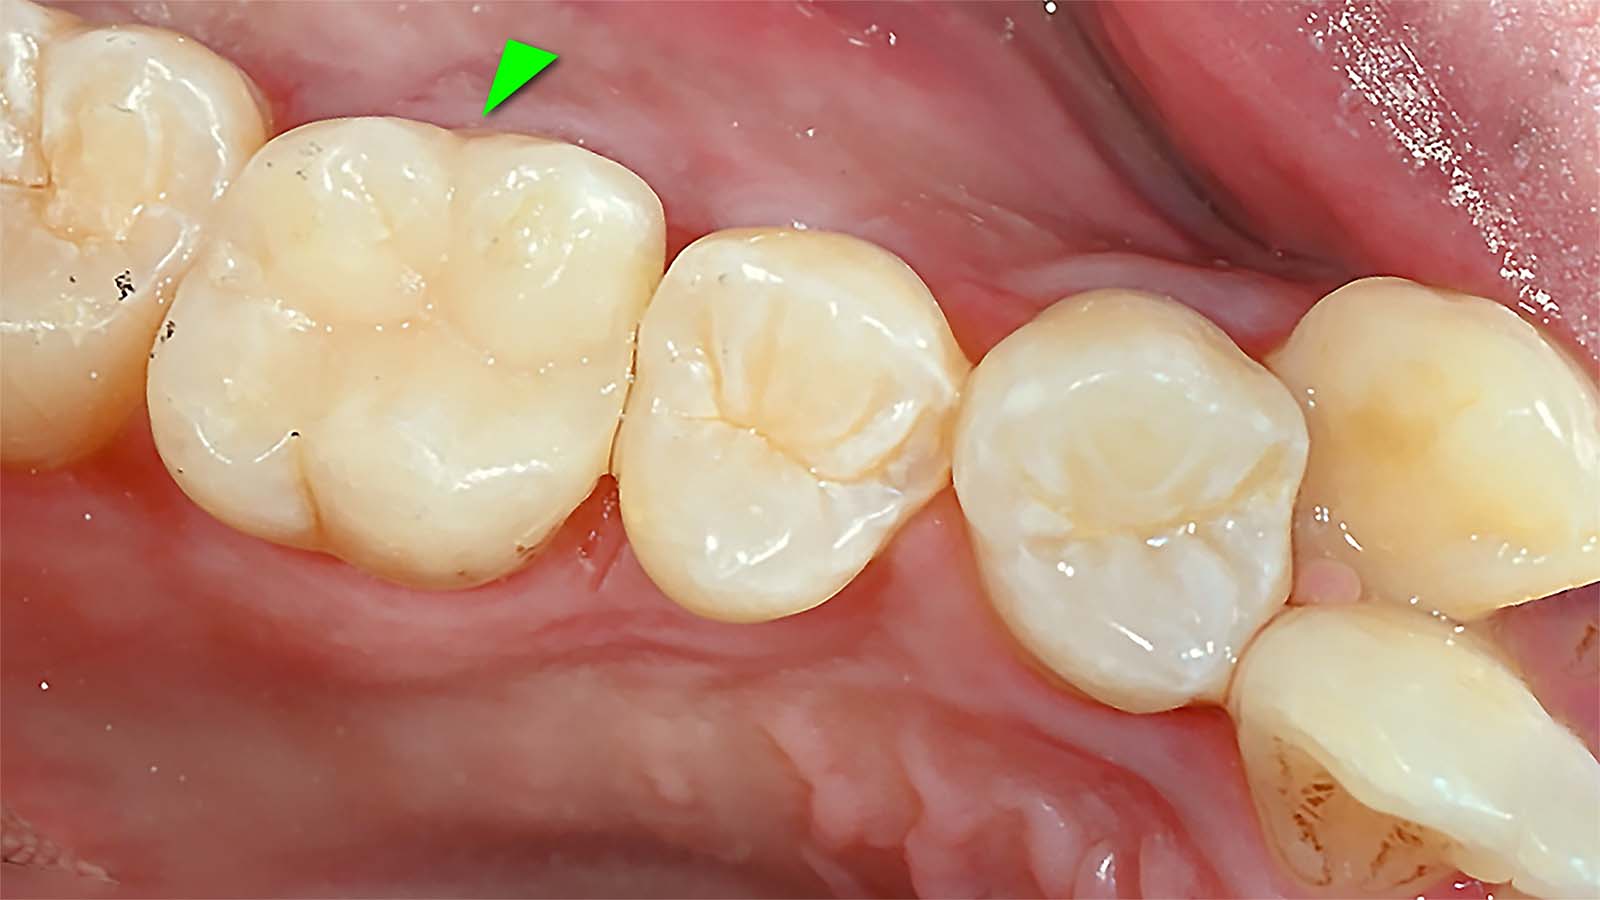

이제 약간의 손재주와 끈기가 필요합니다. 레진을 한 층 한 층 쌓아서 원래의 이상적인 치아의 모습을 만듭니다. 레진 빌드업은 치과의사의 손에서 시작하여 손에서 끝나는 치료입니다. 다음은 레진빌드업 치료결과입니다. 다른 치아와 구분이 안됩니다.

레진빌드업 치료 결과

다음은 레진빌드업으로 치료한 과정을 움직이는 사진(Animated PNG)으로 만든 것입니다. 레진빌드업으로 치료한 치아는 다른 치아와 전혀 구분이 안됩니다.

레진빌드업 치료 과정